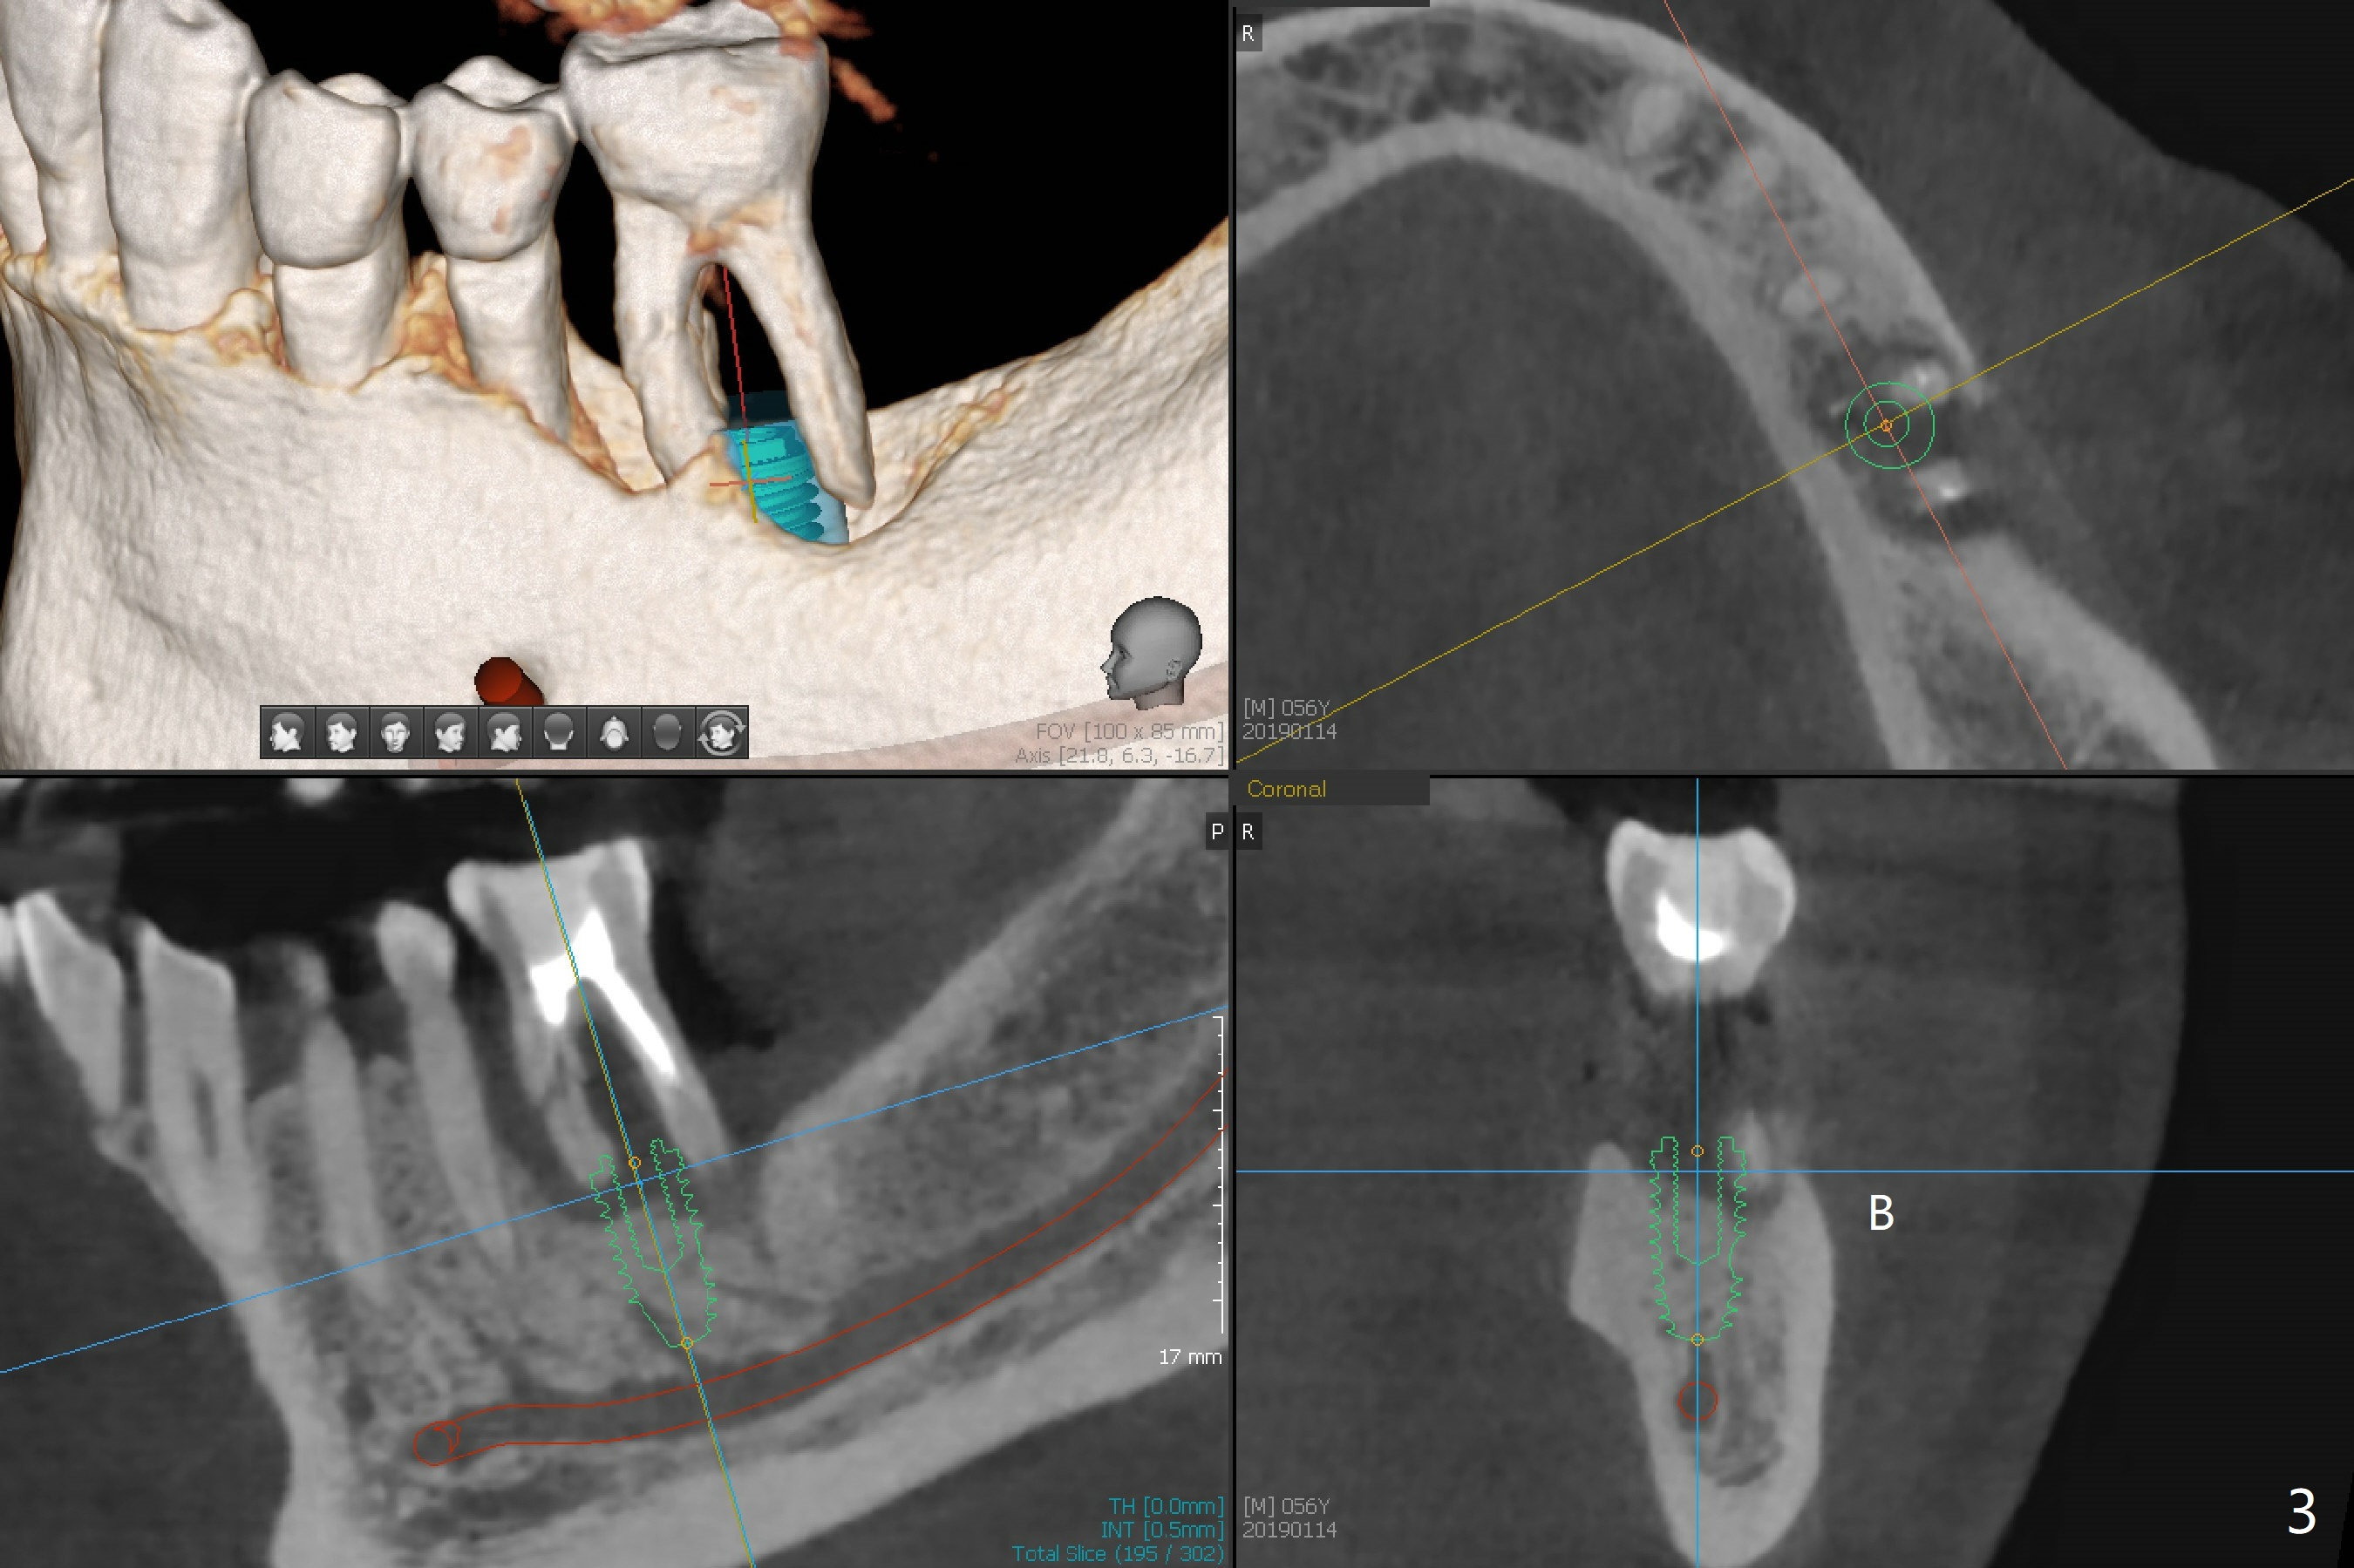

Placement M

When the patient finally agrees to have the tooth #19 to be extracted for implant (Fig.1), there is also mesial bone loss associated with mesial root fracture (Fig.2). To avoid truncation of the blood vessels toward the apex of the tooth #20 (Fig.2 black shadow and red line; Fig.4-6 (lab design) red symbols), a 5x10 mm implant will be placed more distal than the earlier design when the septum was present. The implant is also to be placed slightly higher than the native bone to improve crown/implant ratio; i.e., equical to the buccal, lingual and distal crests (Fig.3-6). Allograft will be placed in the gaps. After distal placement with minor axial change, new treatment plan is born. Return to Lower Molar Immediate Implant, Prevent Molar Periimplantitis (Protocols, Table), Trajectory, Weichat Xin Wei, DDS, PhD, MS 1st edition 01/14/2019, last revision 12/28/2019